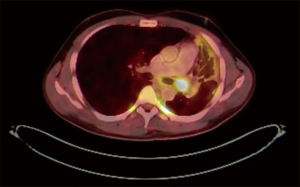

PET CT scan showed the presence of an endobronchial tumour in the left main bronchus (Figure 1). There was some aeration of left lower lobe with a collapse consolidated upper lobe. Endobronchial Biopsy was haemorrhagic. Histopathology suggested the presence of chronic inflammatory cells with no evidence of malignancy. Acid fast bacilli were negative on microscopy and culture. A preliminary diagnosis of endobronchial inflammatory tumour was made and he was scheduled for Robotic resection of Lung.